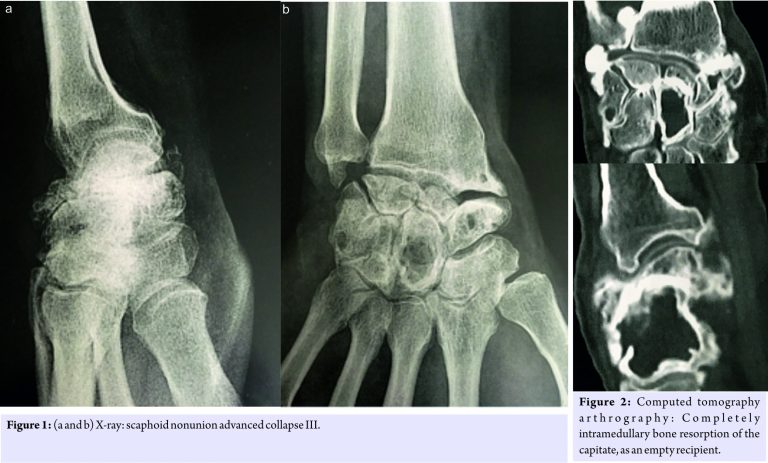

A 55-year-old left-handed man complained of right wrist pain over 5 years. There was no history of systemic illness, steroid abuse, inflammatory disease, or specific trauma. He already had surgery for his SNAC III left wrist: RCPI resurfacing. He also had a history of bilateral carpal tunnel surgery and used to work as a drywall guy. Physical examination: Right wrist: Extension 5°, flexion 10°; left wrist: 20° extension, flexion 20°; no pronation restriction was found in either side. CTA and X-ray showed evolve SNAC III and a completely intramedullary bone resorption of the capitate, as an empty recipient, and a major dorsal synovitis (Fig. 1 and 2).

On the basis of this diagnosis and due to refractory severe pain that did not respond to conservative treatment, we discussed three therapeutic options: PRC with RCPI in case of a possible large bone graft intraoperatively, a pyrocarbon intermediate prosthesis like adaptative proximal scaphoid implant which is interposed between the radius and the second carpal row [7], or a complete arthrodesis of the wrist. We decided to perform an RCPI and bone graft. During surgery, we performed the PRC without any particular difficulty. The cortical bone of the capitate was good quality, and after ablation of endomedullary fibrosis we proceeded to the capitate bone graft with bone chips of 2–3 mm from the lunate and scaphoid, then we were able to implant the RCPI. The prosthesis was stable in all wrist movements. We had an uncomplicated post-operative course, and the patient was subsequently immobilized with a wrist cast for 4 weeks. After 3 months of follow-up, the physical examination in the right wrist showed the following: Flexion 20° and extension 20°, and it was pronation- and supination-free. The patient presented no pain and was satisfied with the operation. The X-ray shows a stable prosthesis (Fig. 3). The 1-year follow-up X-ray (Fig. 4) shows a completely integrated prosthesis.